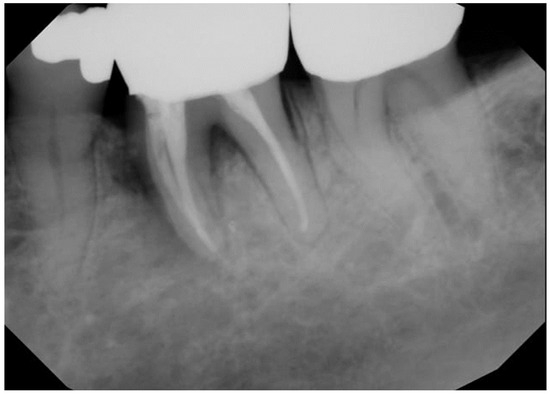

| 1 | M | 69 | Squamous cell carcinoma | Base of Tongue (Oropharynx) | 70 Gy/(Yes) | Mandibular First Molar (#19) | High | Complete Healing |

| 2 | M | 70 | Squamous cell carcinoma | Ventral Tongue/Floor of Mouth (Oral Cavity) [Right] | 70 Gy/(Yes) | Mandibular Incisors and First Molar (#24, #25, #26, and #30) | High | Complete Healing |

| 3 | F | 59 | Squamous cell carcinoma | Tonsil (Oropharynx) [Right] | 70 Gy/(Yes) | Mandibular First Molar (#19) | Moderate | Complete Healing |

| 4 | M | 75 | Adenoid cystic carcinoma | Hard palate/Maxillary Sinus (Oral Cavity) [Left] | 66 Gy/(No) | Mandibular Second Molars (#18 and #31) | Moderate | Complete Healing |